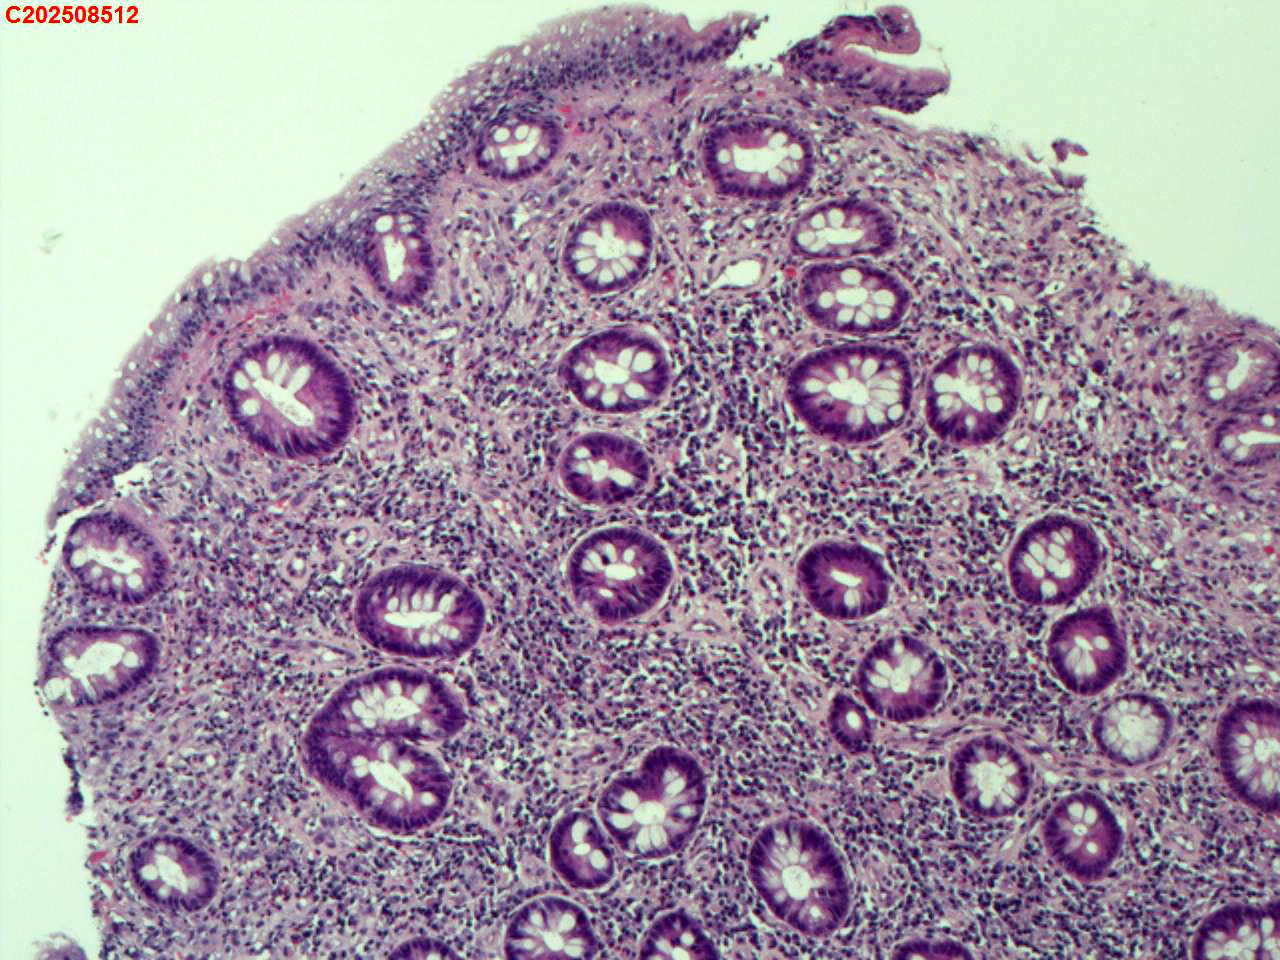

回盲部粘膜

结肠息肉(多发)

一般病史

腹部不适

标本名称

大体所见

回盲部可见一枚直径约6mm息肉样的粘膜隆起。

炎性息肉